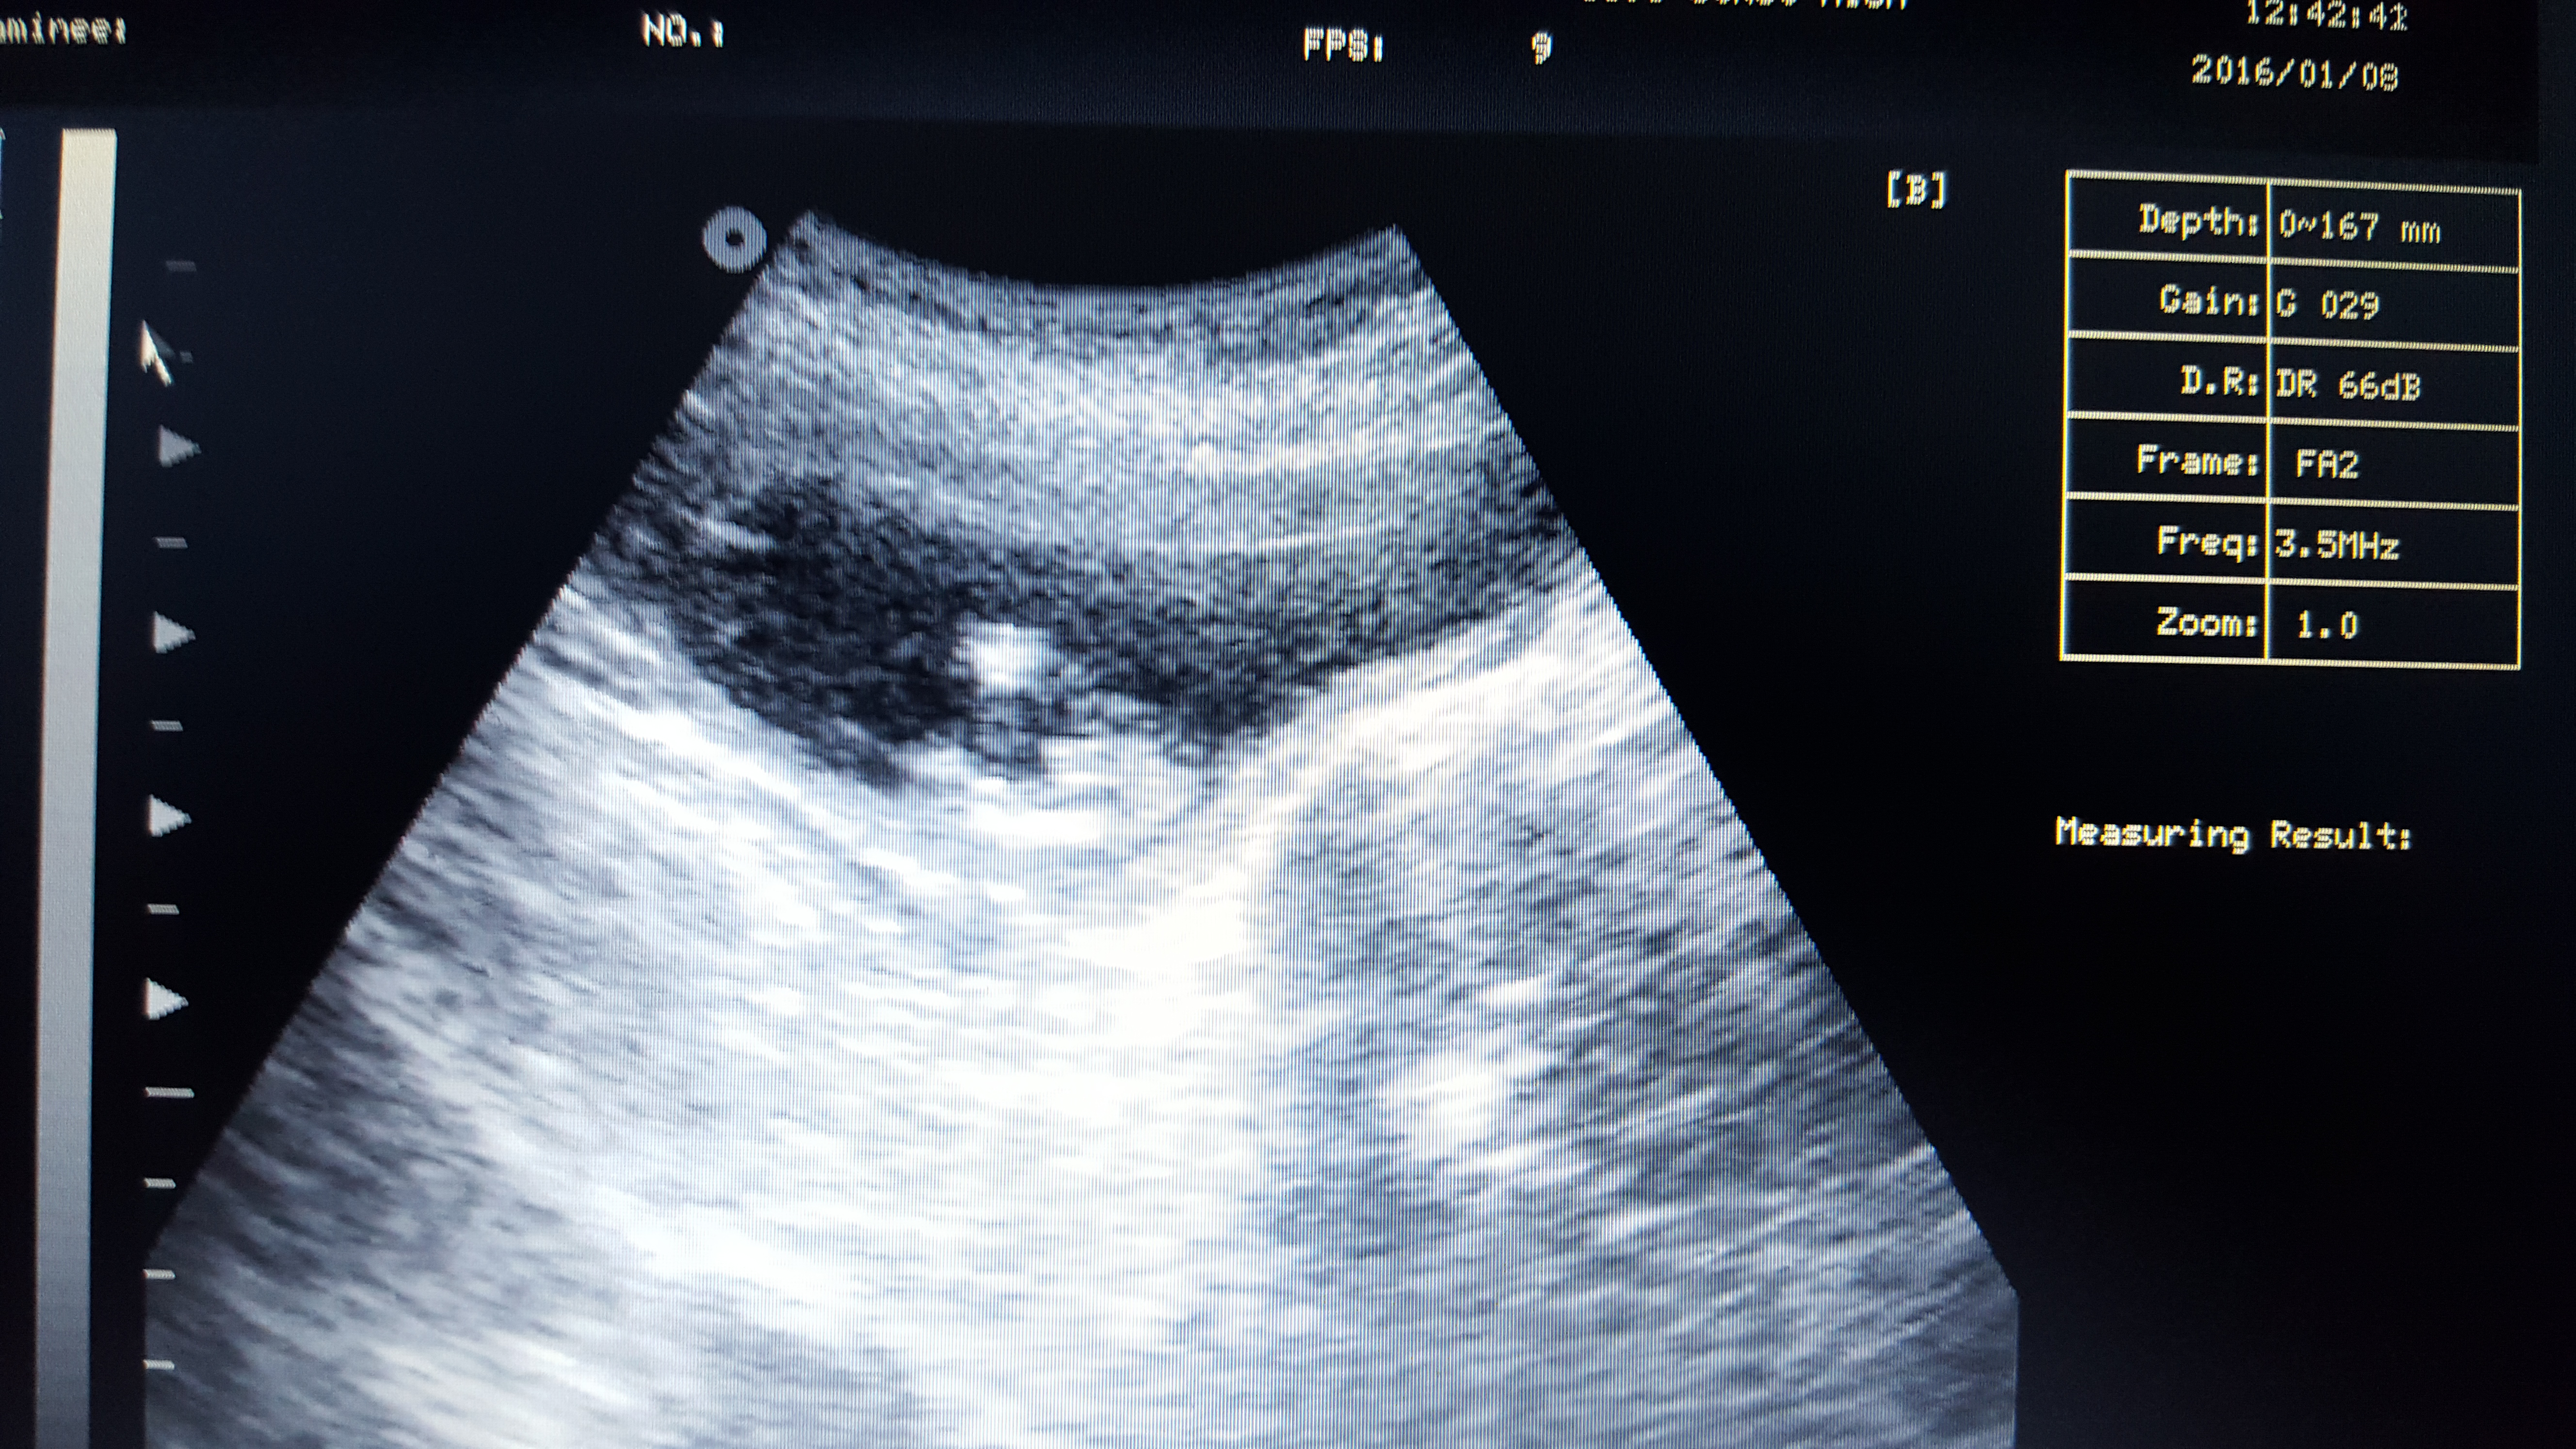

Attachment 29222

This one's a friend, I'm convinced blue but those dots and how early it is does throw me a little, what's everyone else think? Sonographer told her looks girl as the dots aren't protruding as much as a will u would apparantly!